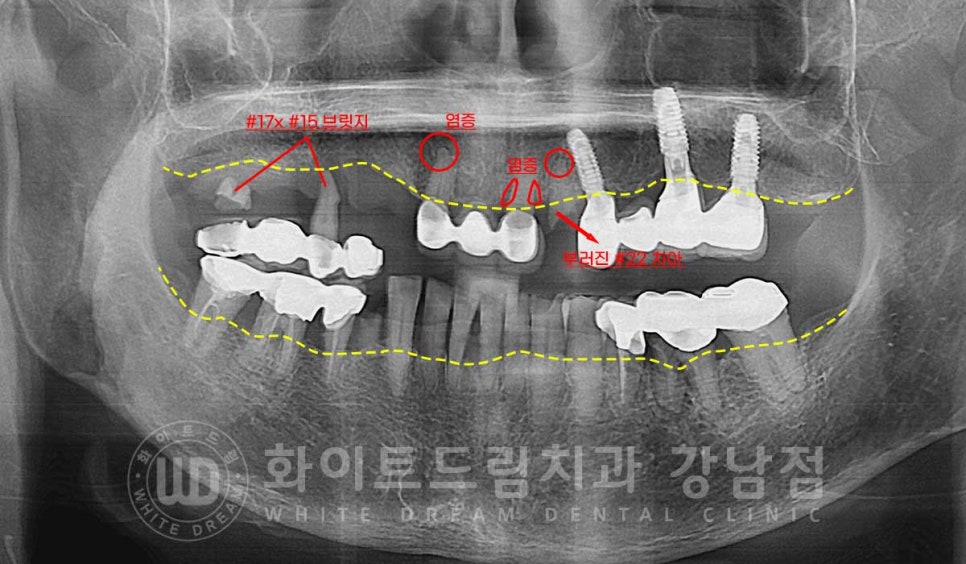

환자분의 초진 x-ray 사진입니다.

타 치과에서 치료를 받으신 20번대 임플란트가 확인되고

그 외 자연치아들은 심하게 흔들리며 치주 질환으로 출혈과 고름이 동반되고 있는 상태였습니다.

특히 10번대 브릿지의 상태가

구강 검진 시 기구로 살짝 건드리니 브릿지가 빠져버릴 정도로

상태가 정말 좋지 못했답니다.

브릿지 지대치 하나는 부러진 상태이고, 남은 지대치가 겨우 버티고 있는 상태였는데

검진시 기구로 살짝 건드리니 지대치가 자연 발거되버렸답니다.